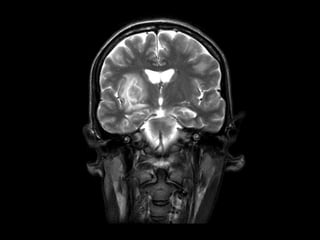

RNM de crânio: lesões multifocais supra e

infratentoriais sugestivas de processo

infeccioso/inflamatório relacionado à infecção

oportunista (neurotoxoplamose).

Demais exames sem alterações, incluindo líquor

e sorologia para toxo.

Caso Clínico RNM decrânio: lesões multifocais supra e infratentoriais sugestivas de processo infeccioso/inflamatório relacionado à infecção oportunista (neurotoxoplamose). Demais exames sem alterações, incluindo líquor e sorologia para toxo.